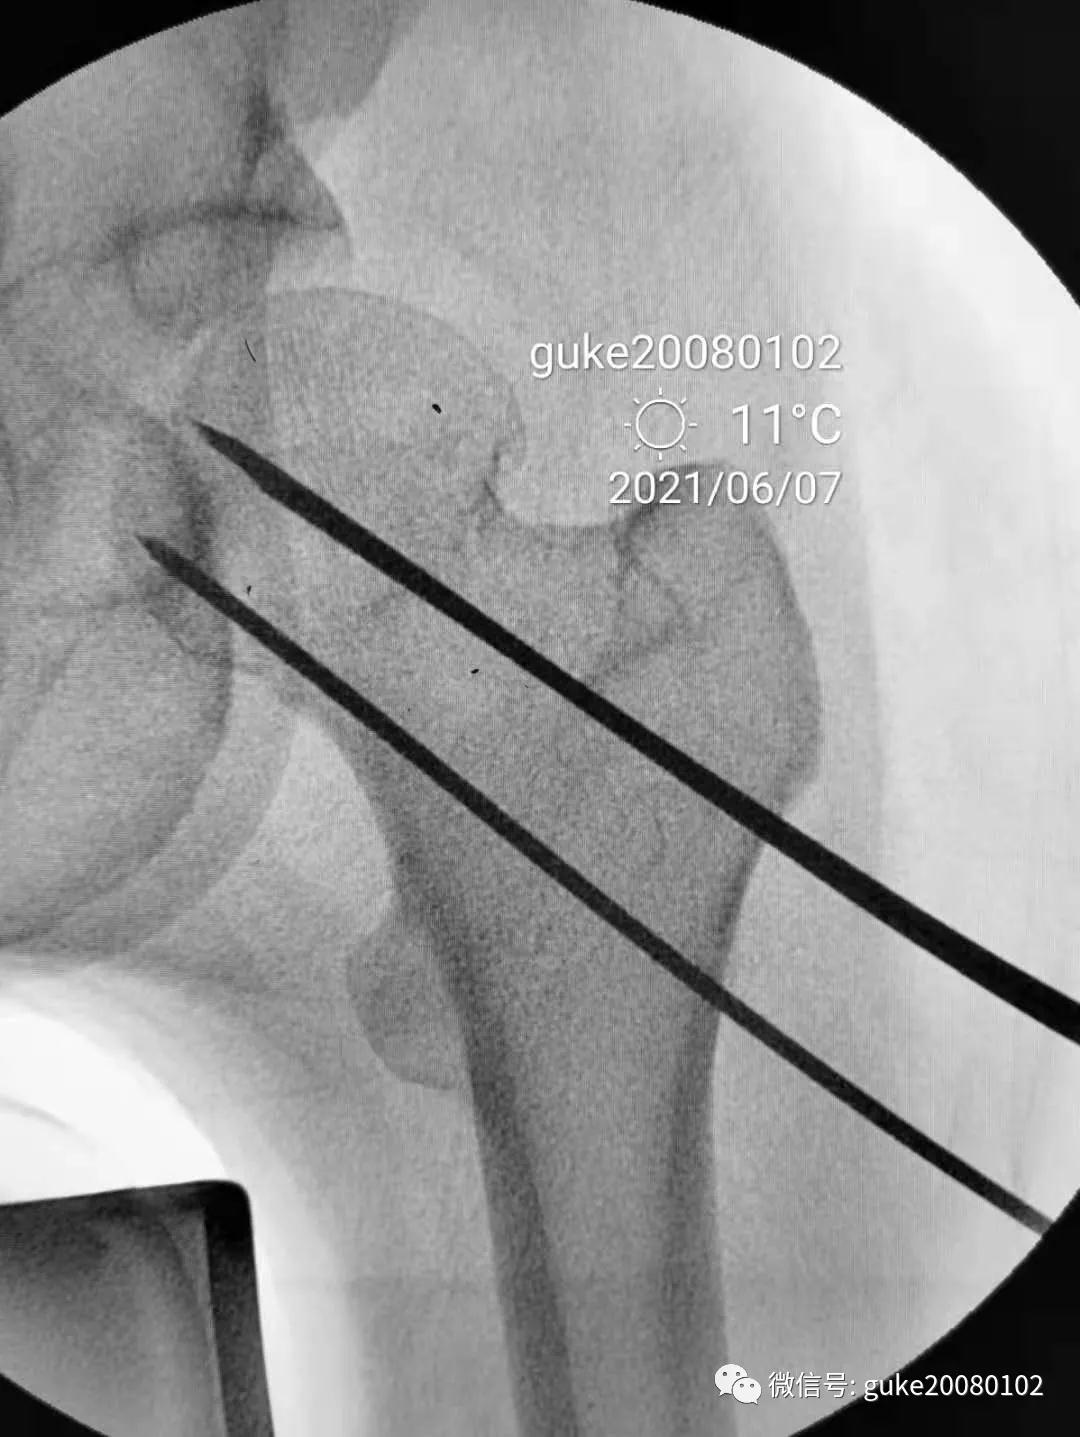

1、植入的第一枚克氏针,前倾和颈干角均满意。将其作为标志针。

2、植入第二枚导针,调整前倾和颈干角。

3、数次调整三枚导针到最合适的位置。

1.顺导针切开皮肤后,空心钻大转子外侧壁开口。

2.拧入三枚直径7.3mm空心钉,并逐步加压,稳定骨折断端。